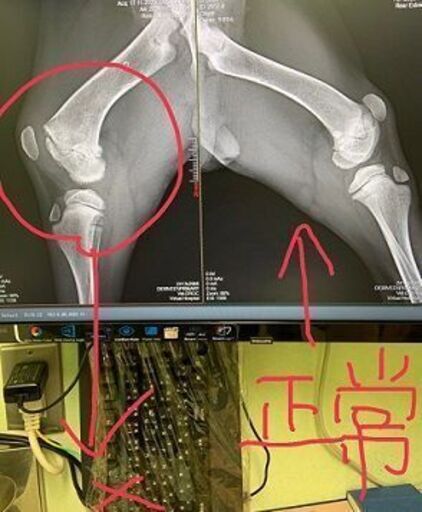

脱臼と靭帯損傷で病院へつれていきました。靭帯損傷は治るとおもいます。

レントゲンの結果、後ろ足のおさらが骨とくっついていないことが判明。先天性の可能性もあります。成長過程で治らない場合は成犬になってから手術が必要になるかもしれません。

おさらがくっつかない場合大きくなってから手術が必要になる可能性がゼロではありません。